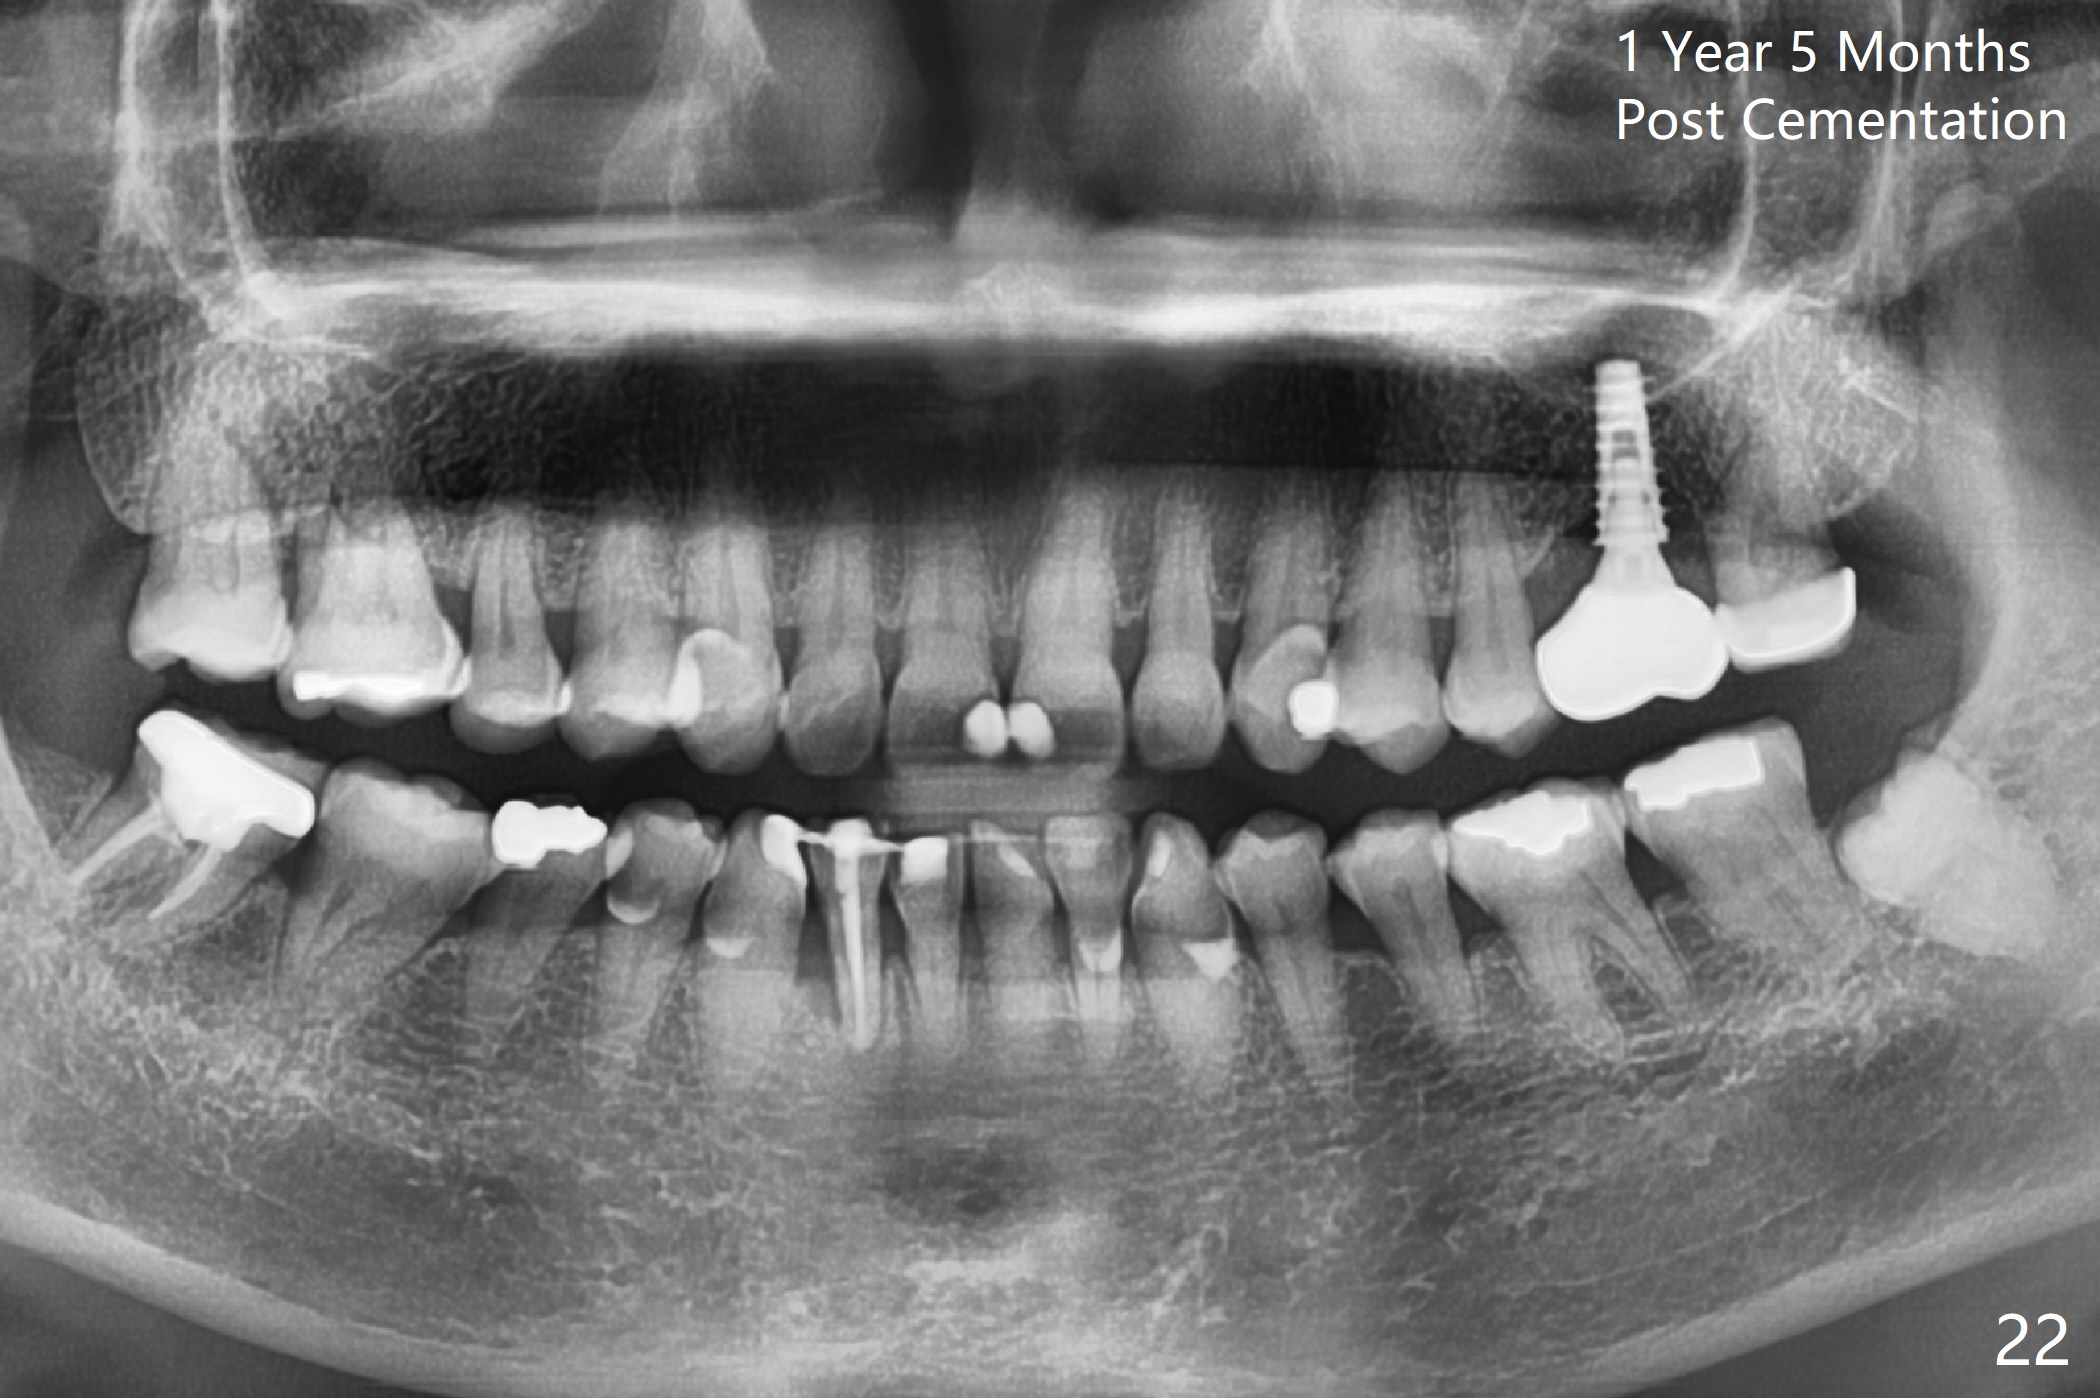

The implant is stable 8 months postop (Fig.15). When a 6x4(3) mm abutment is placed 8.5 months postop, it is distal (Fig.16). The mesiodistal width is 1-2 mm shorter than that at #3, which suggests the mesial shift of the tooth #15. A provisional is fabricated at #14 (Fig.17 P) with supra-occlusion so that there is clearance between the tooth #15 and the opposing one (Fig.18 *). With a separator placed between #14 and 15 (Fig.19), the latter is free to be distalized. Bone volume and density seem to increase 4.5 and 10.5 months post cementation (Fig.20,21, as compared to Fig.15), although the buccal plate remains as concave as shown in Fig.18. One year 5 months post cementation, the patient complains of bad smell from the implant when water pik is being used. It appears that the 1st 2-3 threads are exposed (Fig.22), although the surrounding gingiva remains uninfected. Bone graft is recommended. The site heals without bad smell 7 months post bone graft (2 years 4 months post cementation, Fig.23). The 1st implant thread is found exposed buccal on uncover (regraft?). A small healing abutment is placed because the implant is placed distal (Fig.24). An angled abutment should be tried and #15 crown will be redone. Impression will be taken when the gingiva heals around the provisional crowns.